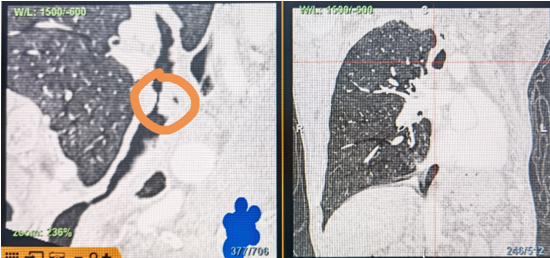

時間就是生命!了解患者病情后,歐陽海峰立刻啟動氣道梗阻緊急救治通道,協(xié)調(diào)院前轉(zhuǎn)運(yùn),急診快速入院流程。凌晨患者入院胸部CT顯示,現(xiàn)存唯一的呼吸通道在右主支氣管處,狹窄處僅約3毫米,患者命懸一線!

運(yùn)用呼吸介入技術(shù),軟硬鏡結(jié)合快速開通氣道,是患者目前唯一可行的治療方案,手術(shù)刻不容緩!但存在麻醉后氣道完全塌陷閉合、大出血、窒息等巨大風(fēng)險?;颊叽饲敖舆B轉(zhuǎn)診3家醫(yī)院,均建議保守支持治療或轉(zhuǎn)院。歐陽海峰詳細(xì)了解患者病史,全面評估影像檢查結(jié)果后,決定盡快進(jìn)行手術(shù),組織醫(yī)護(hù)團(tuán)隊(duì)對患者進(jìn)行持續(xù)密切監(jiān)測,充分保障其術(shù)前安全。